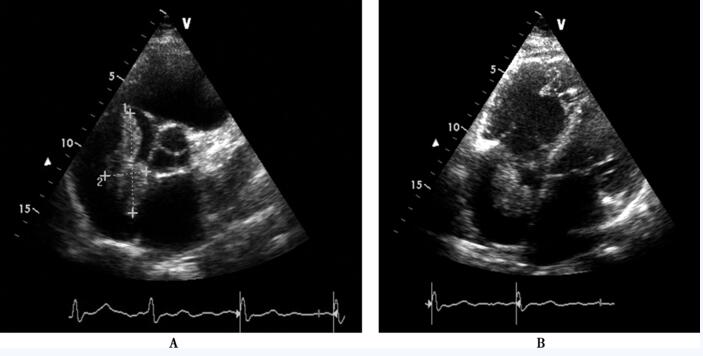

超声心动图:右心房内可见实性强回声团块(图85-1),该团块自下腔静脉延续至右心房内 (图85-2),收缩期突入右心室,舒张期回纳至右心房;下腔静脉近心端可见两束条索样回声,与上述右心房内占位性病变相连续;彩色血流多普勒显示收缩期三尖瓣房侧见大量反流信号。超声诊断:心内平滑肌瘤病。

图85-1 超声心动图提示右心房内占位性病变 A:胸骨旁大动脉短轴切面示右房内可见一大小约26mm×63mm偏强回声团块,与右心房壁无明显粘连;B:胸骨旁四腔心切面示右心房内占位性病变